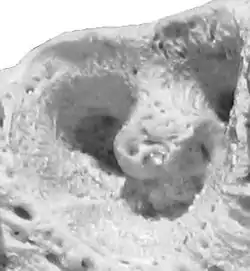

![]() Alveola of the second premolar tooth in a bovine maxillary bone | |